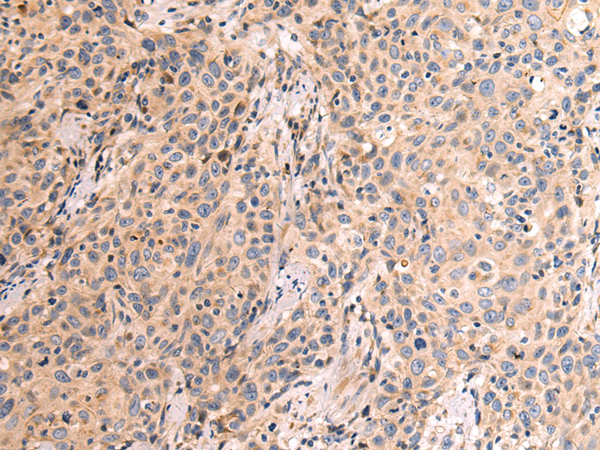

IHC positive control:

Human prostate cancer

IHC Recommend dilution:

50-200